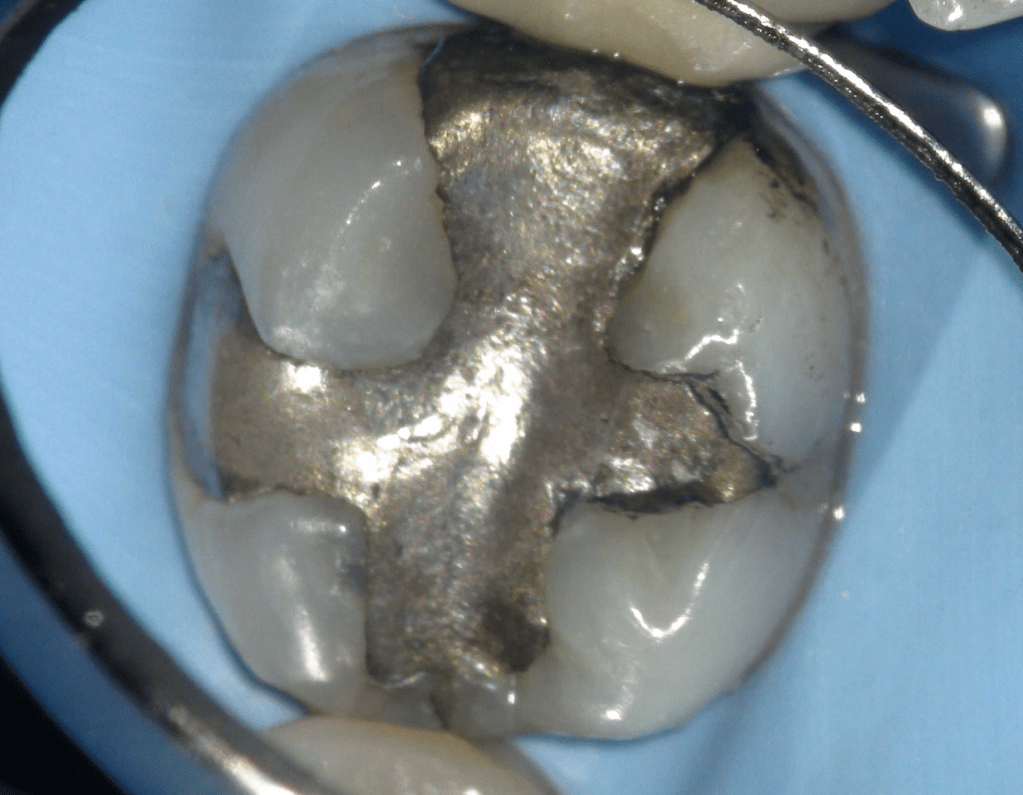

Fisura, remoción amalgama para explorar